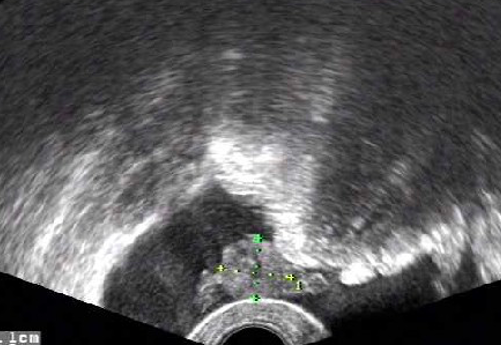

宫颈处的液性暗区

图片

图源:作者

① 宫颈囊肿:小的宫颈囊肿无特殊临床意义,多发的较大囊肿可致宫颈增大,声像图上见宫颈前后唇内圆形或类圆形无回声区,无明显的壁,后方回声增强,囊肿合并感染时,囊内无回声区内可出现密集点状中等回声,此时常可见宫腔线液性分离。

② 宫颈电切术后:电切术后,宫腔内可见少量无回声区分布。

③ 宫颈癌:宫颈增大,呈「菜花」状,超声检查提示宫颈内回声不均匀,可见粗大的高回声斑点或团块状的低回声。如发生颈管浸润阻塞,还可见宫腔扩张积血形成的暗区。